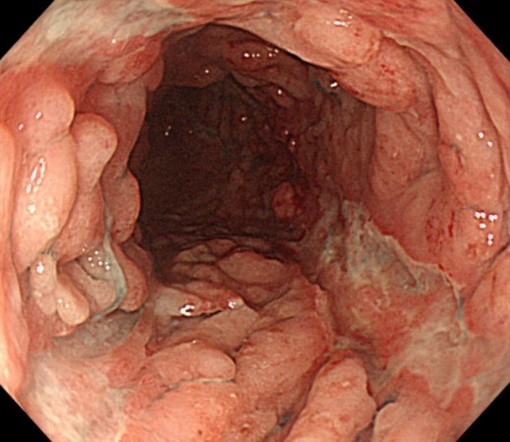

炎症性腸疾患(Inflammatory Bowel Disease; IBD)は潰瘍性大腸炎とクローン病に分類されます。どちらも腸に慢性に炎症が起きる病気で原因がわかっておらず難病に指定されています。日本の患者数は増加傾向で潰瘍性大腸炎22万人、クローン病7万人以上いると推定されています。20~30歳代に発症することが多く就学、就労などへの影響も大きい疾患です。現在当院では潰瘍性大腸炎(UC)の方が約350名、クローン病(CD)の方が約100名、診療を受けています。

上記のような薬物療法を行っても、症状が改善せず、悪化した場合や症状が改善しない場合、十分な治療を行っても生活の質が低下した状態が続く場合などには、手術によって大腸を切除する場合があります。大量の出血、大腸の穿孔(大腸の壁が破れる)、巨大結腸症(大腸の壁が薄くなり、風船のように膨れる)などの場合は生命に関わる状態ですので、緊急で手術を行います。そのほか、発症してからおおよそ8年以上経過した方では大腸がんやその前がん病変が生じる場合があり、この場合も大腸を切除する手術が必要となります。